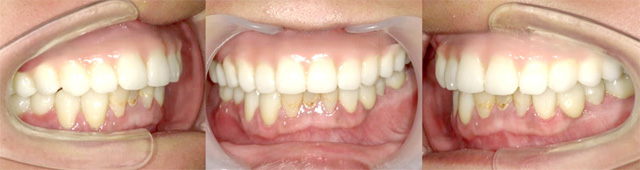

オールオン4の治療例:1

治療前

治療後

オールオン4の治療例:2